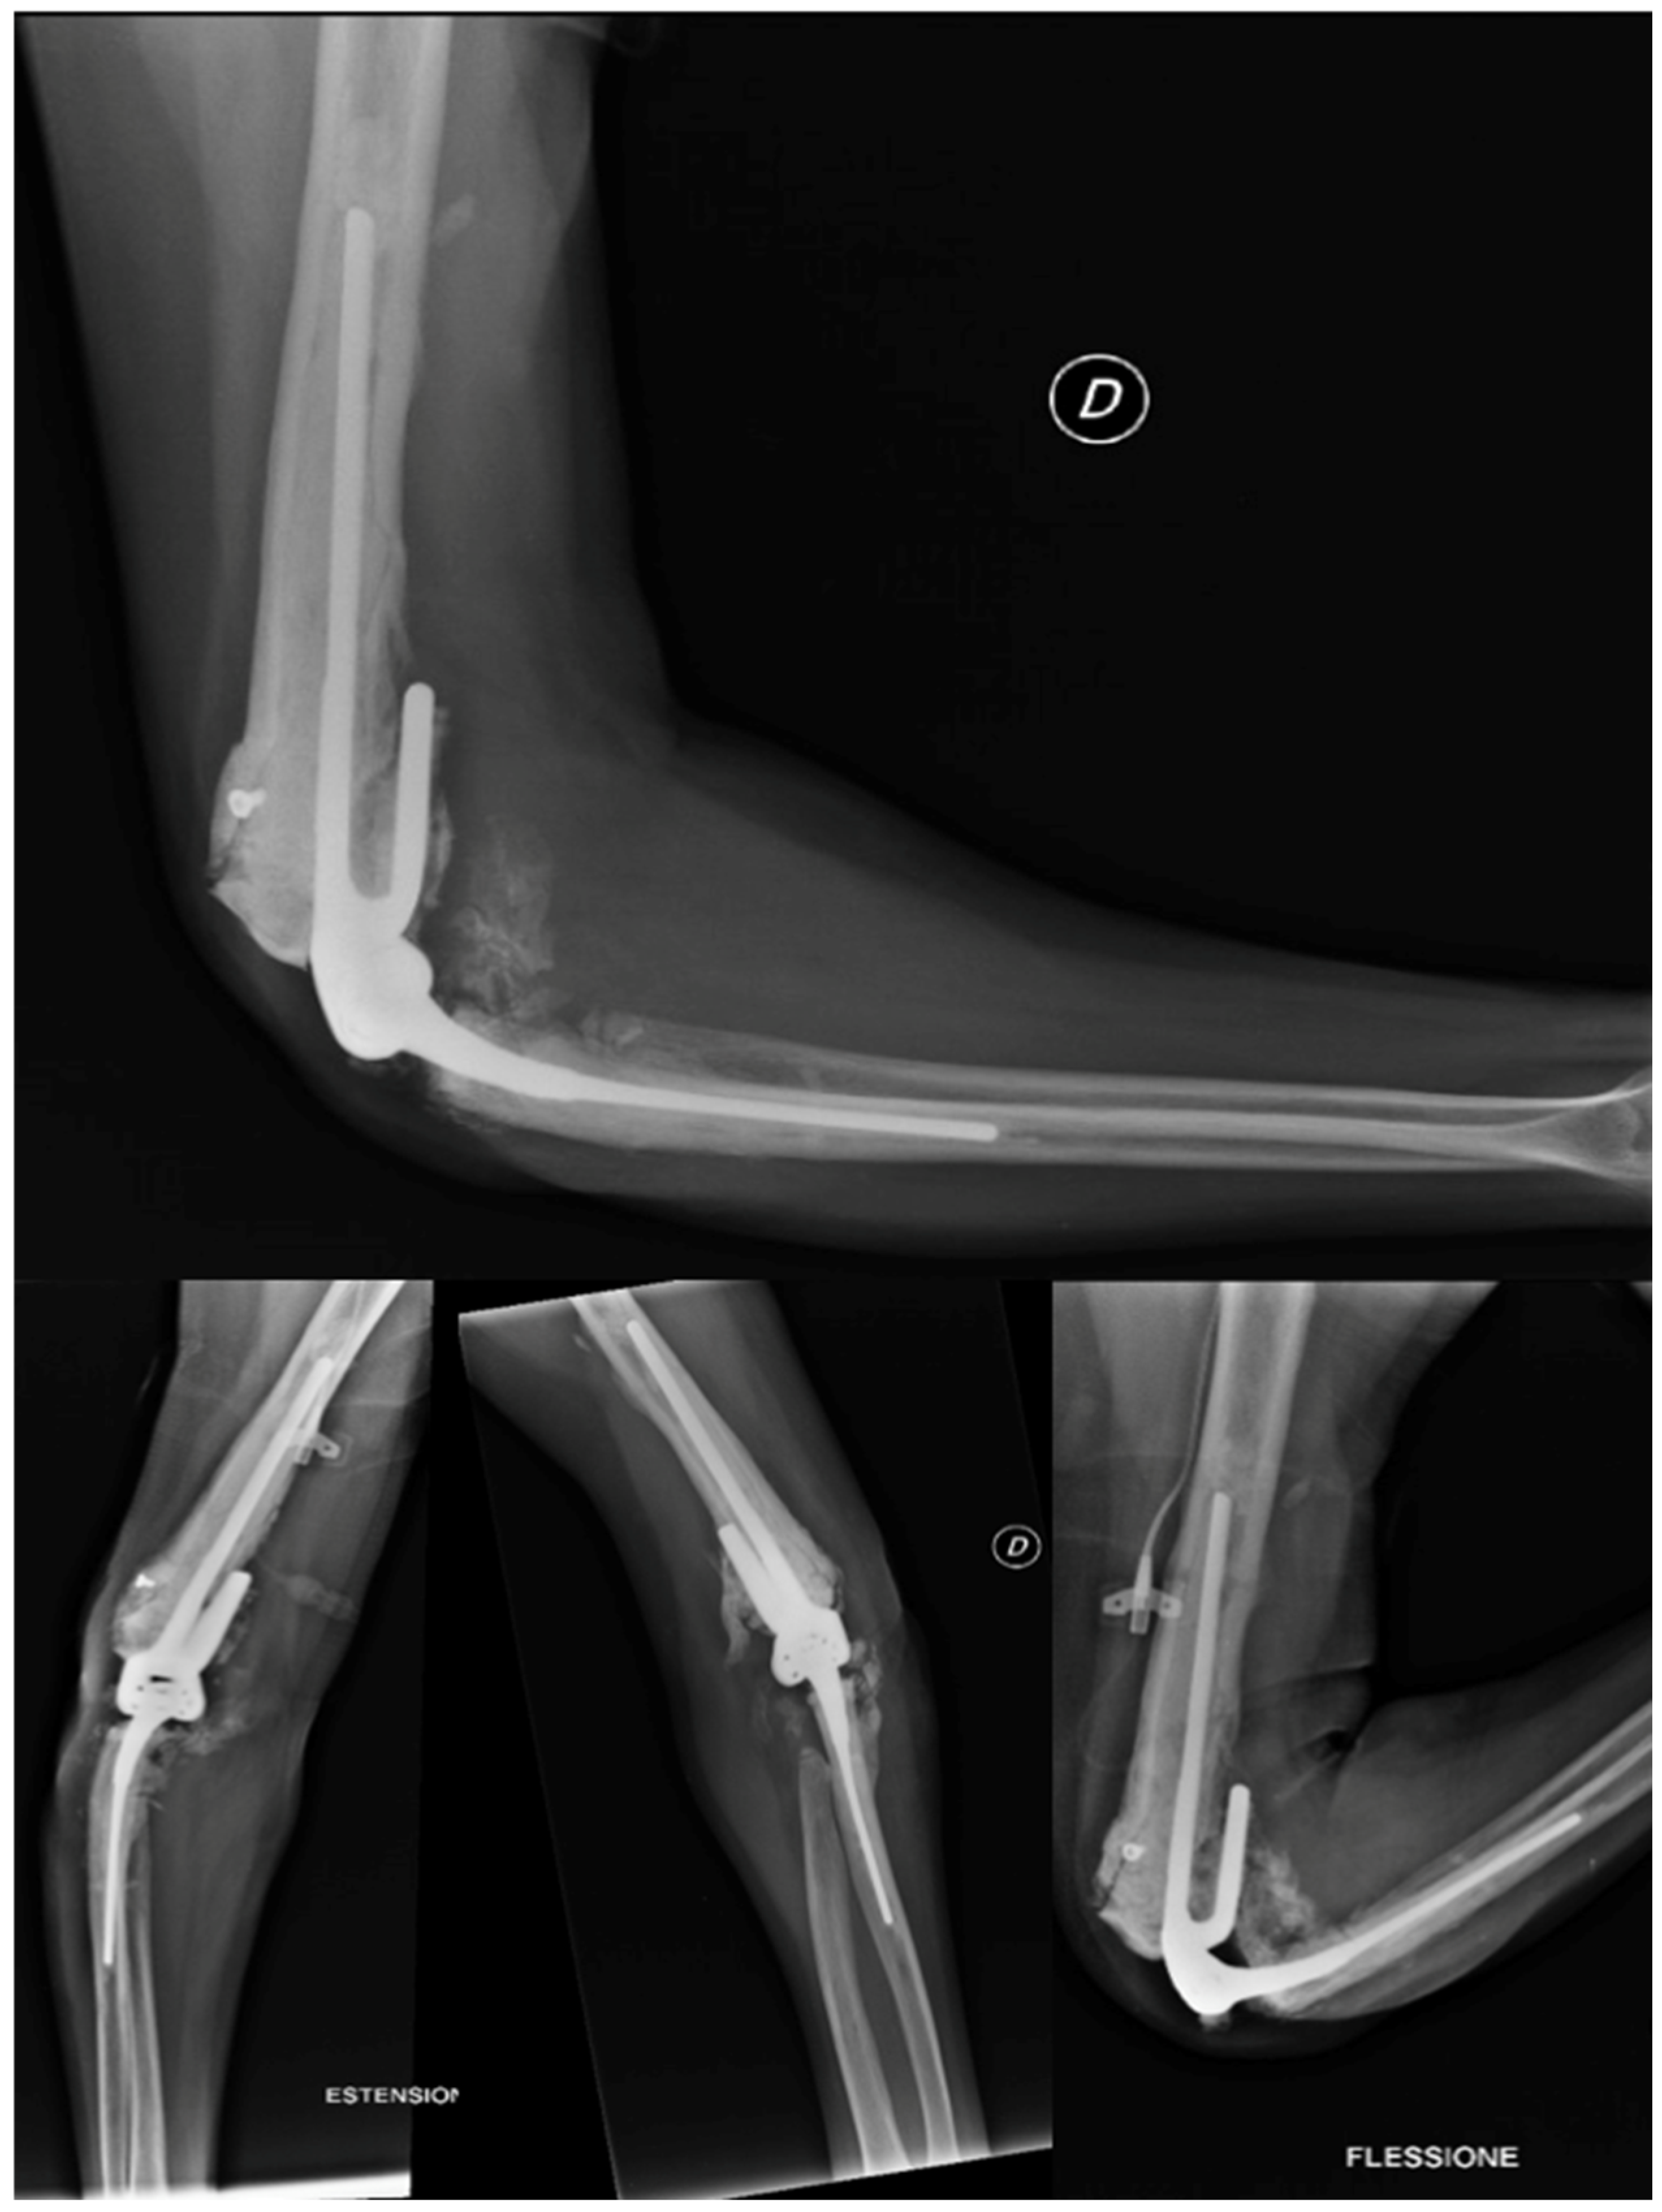

2.4.6. Revision Total Elbow Arthroplasty

In January 2014, a surgical procedure was conducted via the conventional lateral access approach to replace the prosthesis with a Coonrad–Morrey humeral stem small/L 150 mm/Flangia by thorough irrigation and cementation in the absence of any signs of infection in the operating room. The patient was instructed to keep the arm in a sling for a month. Due to the arthrodesis failure and the good fit of the ulnar component, prosthetic revision was deemed the most appropriate option. Postoperative radiography demonstrated appropriate implant placement.

The patient had a good postoperative course, except for a small wound dehiscence with fibrinous serum secretions, which resolved in May 2014 with outpatient clinic treatments. In July 2014, after four months, the patient achieved complete extension and flexion of 100°, with no significant changes in the radiographic findings. Two months later, in September 2014, the radiographs remained unchanged, as shown in Figure 10, and the patient had a flexion of approximately 105°, complete extension and pronation, and limited supination of 5°.

Figure 10.

X-ray anteroposterior, lateral in neutral position, in extension and in flexion views of the right elbow at 6 months after the second revision surgery. No signs of loosening. Good alignment of the implant in neutral position and in flex–extension position.